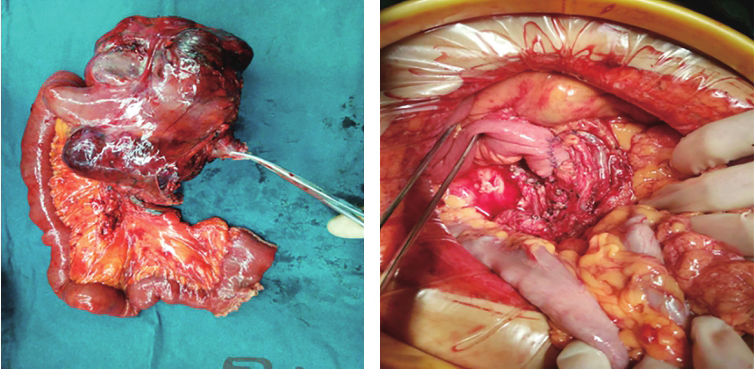

患者经输血补液,复查血常规示:血红蛋白73g/L。再次输入悬浮红细胞5U,于入院第四天在全麻下行剖腹探查术,术中探查见:上腹部一15.0cm×15.0cm肿瘤性病变,肿瘤似来源于十二指肠水平部,十二指肠及上段空肠包绕肿瘤,肿瘤有包膜,血供丰富,上达胰腺下缘,右侧达胰腺钩突部,左侧位于降结肠系膜后方,肠系膜上动静脉位于肿块右后方,肾静脉自肿瘤后方穿过,决定行十二指肠肿物切除术,手术过程顺利,术后标本及腹腔情况见图2。

术后病理:(十二指肠水平部)胃肠间质瘤。肿块大小约14.0cm×10.0cm×6.0cm,细胞梭形、轻度异型、核分裂象>5个/50HPF;送检肠管两手术切缘未见肿瘤累及。改良NIH危险度分级:高危。

图2 术后标本及腹腔情况